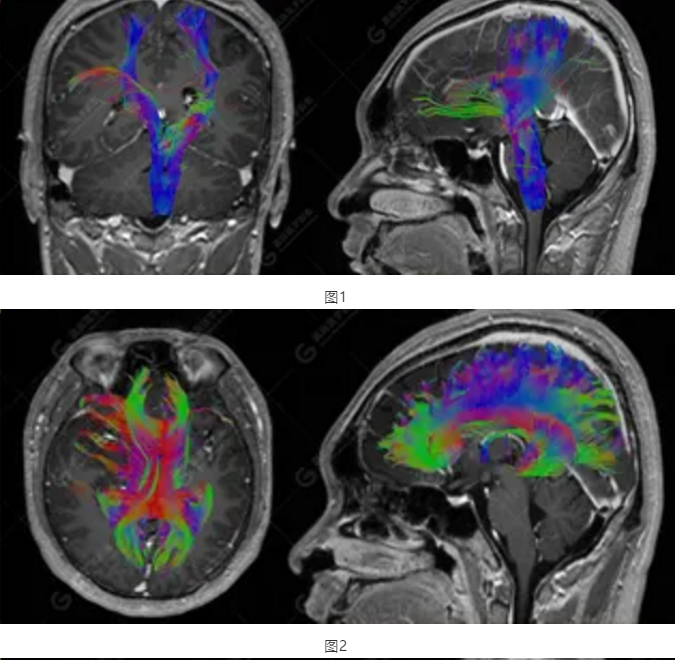

以上為DTI成像,圖1為皮質(zhì)脊髓束,圖2為胼胝體束,圖3為扣帶回束,圖4為額枕束。DTI成像示右側(cè)額枕束前部明顯受壓、部分未見(jiàn)顯示;胼胝體束、雙側(cè)扣帶束、皮質(zhì)脊髓束及左側(cè)額枕束形態(tài)可,纖維束未見(jiàn)明顯破壞,未見(jiàn)明顯稀疏減少。

2.DTI成像示右側(cè)額枕束前部明顯受壓、部分未見(jiàn)顯示。